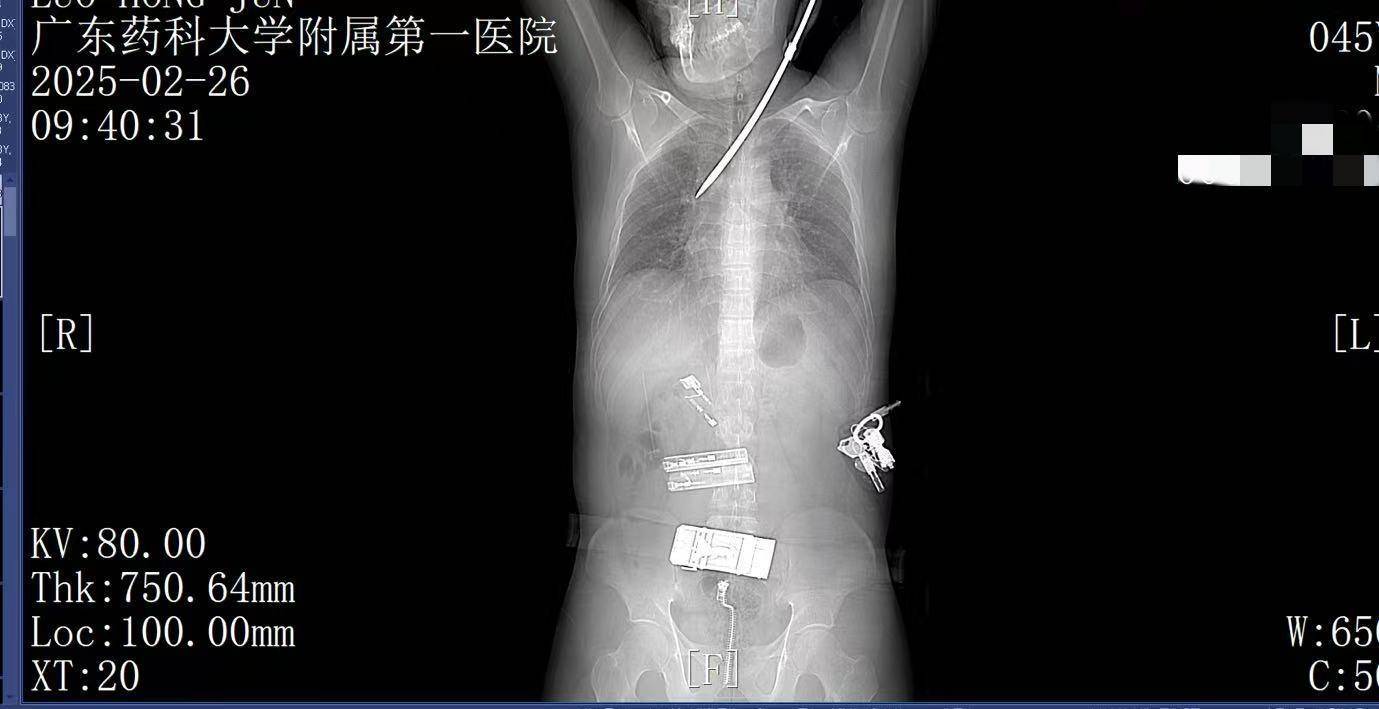

9:41,快速完成头+胸+腹部CT检查,经多学科会诊,明确螺丝刀异物刺入肺部。CT显示螺丝刀紧贴肋间血管、上肺后段动脉,尖端距右肺门仅2厘米,一旦贸然拔出螺丝刀,极有可能引发大出血,导致失血性休克甚至死亡,必须紧急手术。

9:39,救护车到达医院大门,院内急救团队已经做好准备。在紧密监护的情况下,全程采用绿色通道。到达医院时,罗师傅已经面色苍白,呼吸急促。螺丝刀已深深刺入罗师傅右肺,随时可能因大出血而危及生命。

2月26日上午9时许,44岁的电梯工人罗师傅(化姓)正在广州某工地弯腰工作,突然一把螺丝刀从20多米高处坠落,刺中罗师傅的胸背部。罗师傅当即疼痛难忍,呼吸困难。工友立即呼叫120。一场惊心动魄的生死救援立即展开。